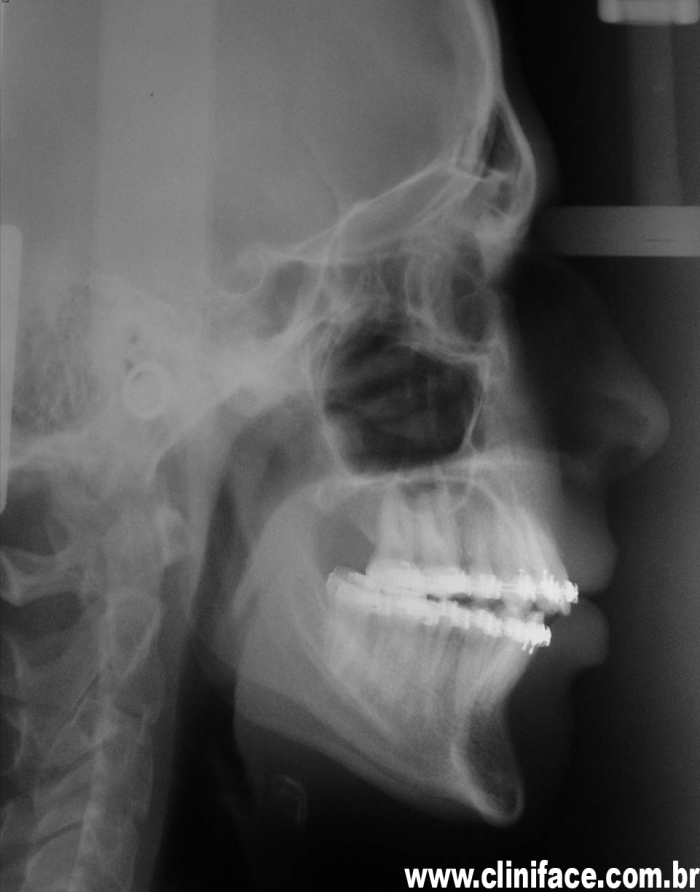

Telerradiografia final